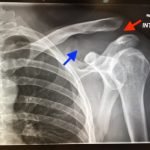

Plain films of the left shoulder showed elevation of the left clavicle above the acromion. There was an increase in the acromioclavicular (AC) and coracoclavicular (CC) distances (increased joint distances marked with red and blue arrows, respectively). A normal AC joint measures 1-3 mm whereas a normal CC distance measures 11-13 mm.1 The injury was classified as a Rockwood type III AC joint separation.